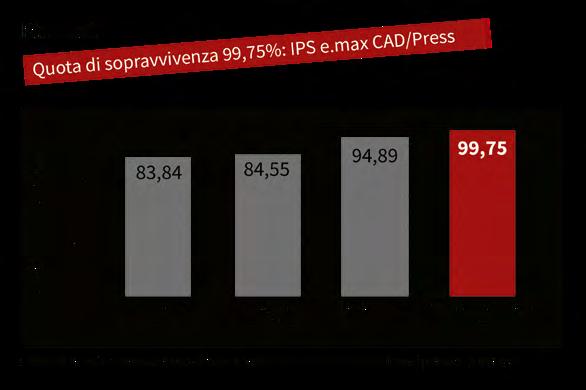

Uno studio di K. A. Malament dimostra: di tutti i materiali cementati IPS e.max ® CAD/Press, con una percentuale di sopravvivenza del 99,75% in un periodo di osservazione di poco più di dieci anni, è risultata essere la ceramica di maggior successo.

Nell’ambito di questo studio dal 1983 sono stati cementati oltre 6000 restauri in ceramica integrale. Sono state descritti quattro diversi tipi di ceramiche: - Dicor/Dentsply Sirona (n = 1504) - In-Ceram/Vita (n = 330) - IPS Empress (n = 2133) - IPS e.max Press o CAD (n = 2364)

Dicor è stato registrato dal 1983, In-Ceram dal 1990, IPS Empress ® dal 1992 e IPS e.max dal 2005.

Sebbene il periodo di osservazione più breve risulti a poco più di dieci anni (128 mesi), i restauri in disilicato di litio in IPS e.max Press e IPS e.max CAD in questa panoramica su larga scala presentano il più alto tasso di sopravvivenza del 99,75 %. Secondo K. A. Malament i materiali hanno soddisfatto rispettivamente superato tutti i requisiti clinici, che nella pratica clinica sono considerati ideali.

IPS e.max fin dall’inizio è stato accompagnato scientificamente. Molti noti esperti da tutto il mondo con i loro studi clinici hanno contribuito ad un eccellente database. Sia per il disilicato di litio che anche per l’ossido di zirconio il tasso di sopravvivenza medio è del 96% ciascuno. Nell’IPS e.max Scientific Report sono riassunti tutti i risultati dello studio in vivo ed in vitro.